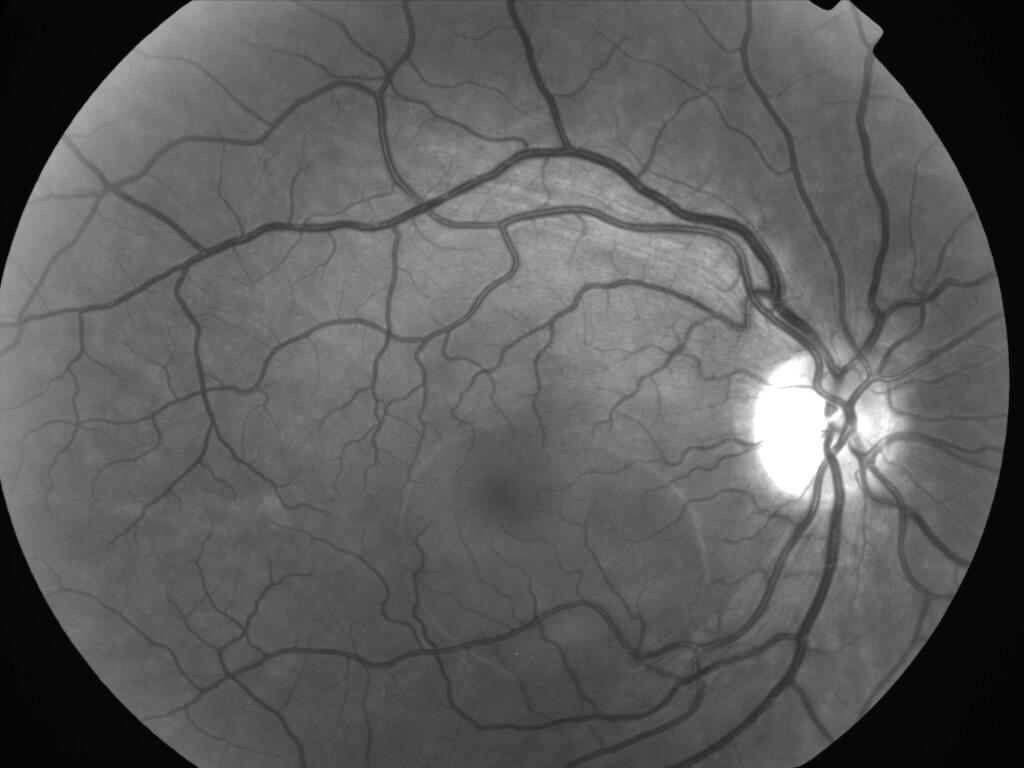

CHORIORETINOPATHIE SEREUSE CENTRALE

IM000001.jpg